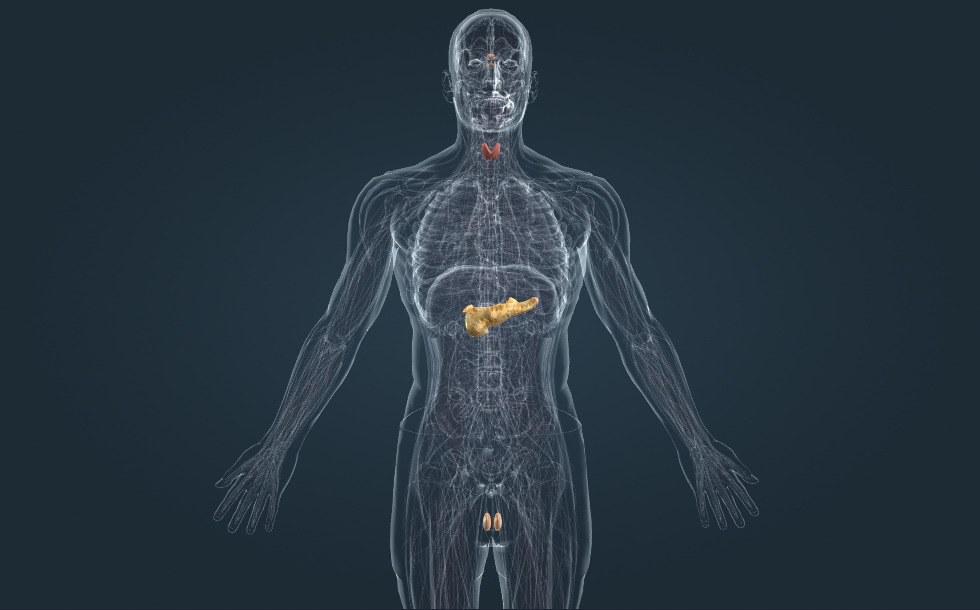

Hormoninė sistema

- prieskydinės liaukos - Jos išskiria prieskydinį hormoną (paratormoną), kuris kraujyje padidina kalcio koncentraciją. Kalcitoninas, prieskydinės liaukos išskirtas hormonas, turi priešingą poveikį: kalcio koncentraciją kraujyje sumažina.

- antinkstis - Jis susideda iš žievės ir medulos. Žievė išskiria hormonus, kraujyje pakeldama gliukozės ir natrio kiekius. Medula gamina epinegriną (adrenaliną) - streso hormoną, turintį didelę įtaką organizmo atsakui į stresą.

- sėklidė - Ji gamina sėklą bei tostesteroną (vyrišką hormoną), kuris skatina sėklos subrendimo procesą bei vyriškos figūros vystymąsi ir kūno plaukų augimą.

- kasa - Ji išskiria insuliną, kuris kraujyje mažina gliukozės kiekį. Insulino trūkumas sukelia diabetą.

- skydliaukė - Ji išskiria T4 (tiroksino) hormoną, kuris padidina biologinę oksidaciją. Jis atlieka svarbų vaidmenį normalaus augimo ir smegenų vystymosi procese. Perteklinė skydliaukės hormono gamyba sukelia Greivso ligą, o hipotirozė sukelia strumą arba kretinizmą (sukeltą įgimtos hipotirozės).

- hipofizės liauka - Kartu su pagumburiu ji sudaro pagumburio-hipofizės ašį - mūsų hormoninės sistemos centrą.

Hormonus gamina endokrininės sistemos liaukos. Adrenaliną išskiria antinksčių liauka, insuliną kasa, o tiroksiną skydliaukės liauka.

Endokrininės sistemos centras - pogumburio hipofizės ašis. Pogumburis gamina hormonus, reguliuojančius hipofizės liauką, kurioje skatina kitų hormonų gamybą. Šie hormonai skatina kitų endokrininių liaukų darbą: skydliaukės, antinksčių ir lytinių liaukų. Pogumburio-hipofizės ašis nereguliuoja kasos veiklos.